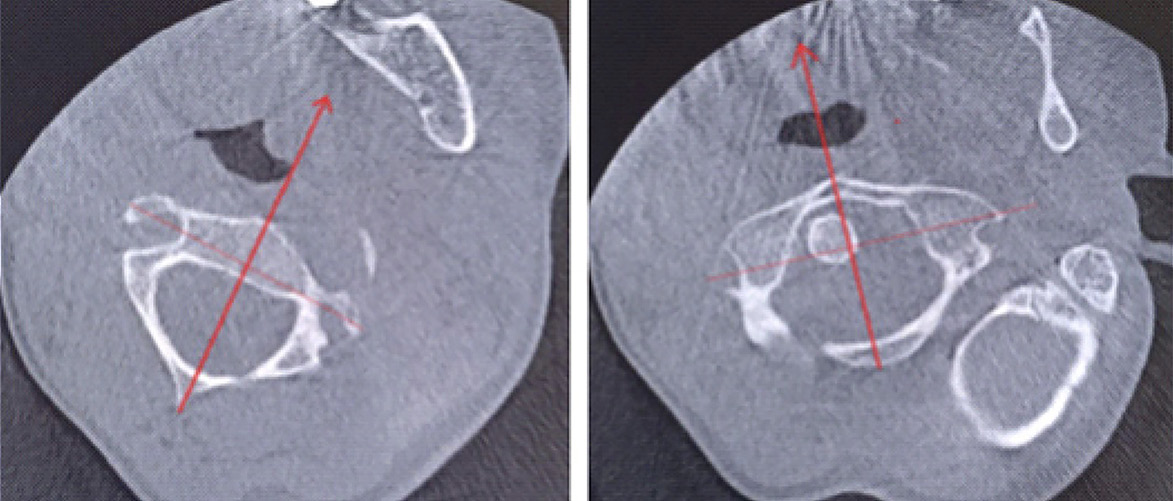

Было принято решение провести лечение в амбулаторных условиях, осуществляя устранение подвывиха с помощью бандажа для жесткой фиксации шейного отдела позвоночника, в виде постоянного ношения сроком на 7 дней. Кроме этого, был проведен курс лечебной гимнастики под контролем врача по лечебной физической культуре. По данным контрольного исследования КЛКТ, выполненной через 7 дней, отмечалась положительная динамика в виде уменьшения угла ротации атланта до 8° и восстановления конгруэнтности суставных поверхностей латерального атлантоаксиального сустава слева (рис. 4).

Рис. 4. Наложение изображений атланта и аксиса в аксиальной плоскости на контрольном исследовании после лечения